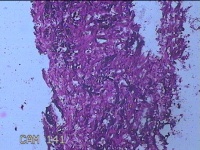

左前臂结节

性别

女

年龄

46岁

临床诊断

皮脂腺囊肿

发现左前臂结节4个月余,无明显疼痛及不适。

标本名称

大体所见

灰白暗红色组织1.3x0.8x0.3cm一块,表面带梭形皮肤1.2x0.3cm,皮下见结节1x0.8x0.3cm一个,切开结节呈实性,切面灰白粉红色,质软。